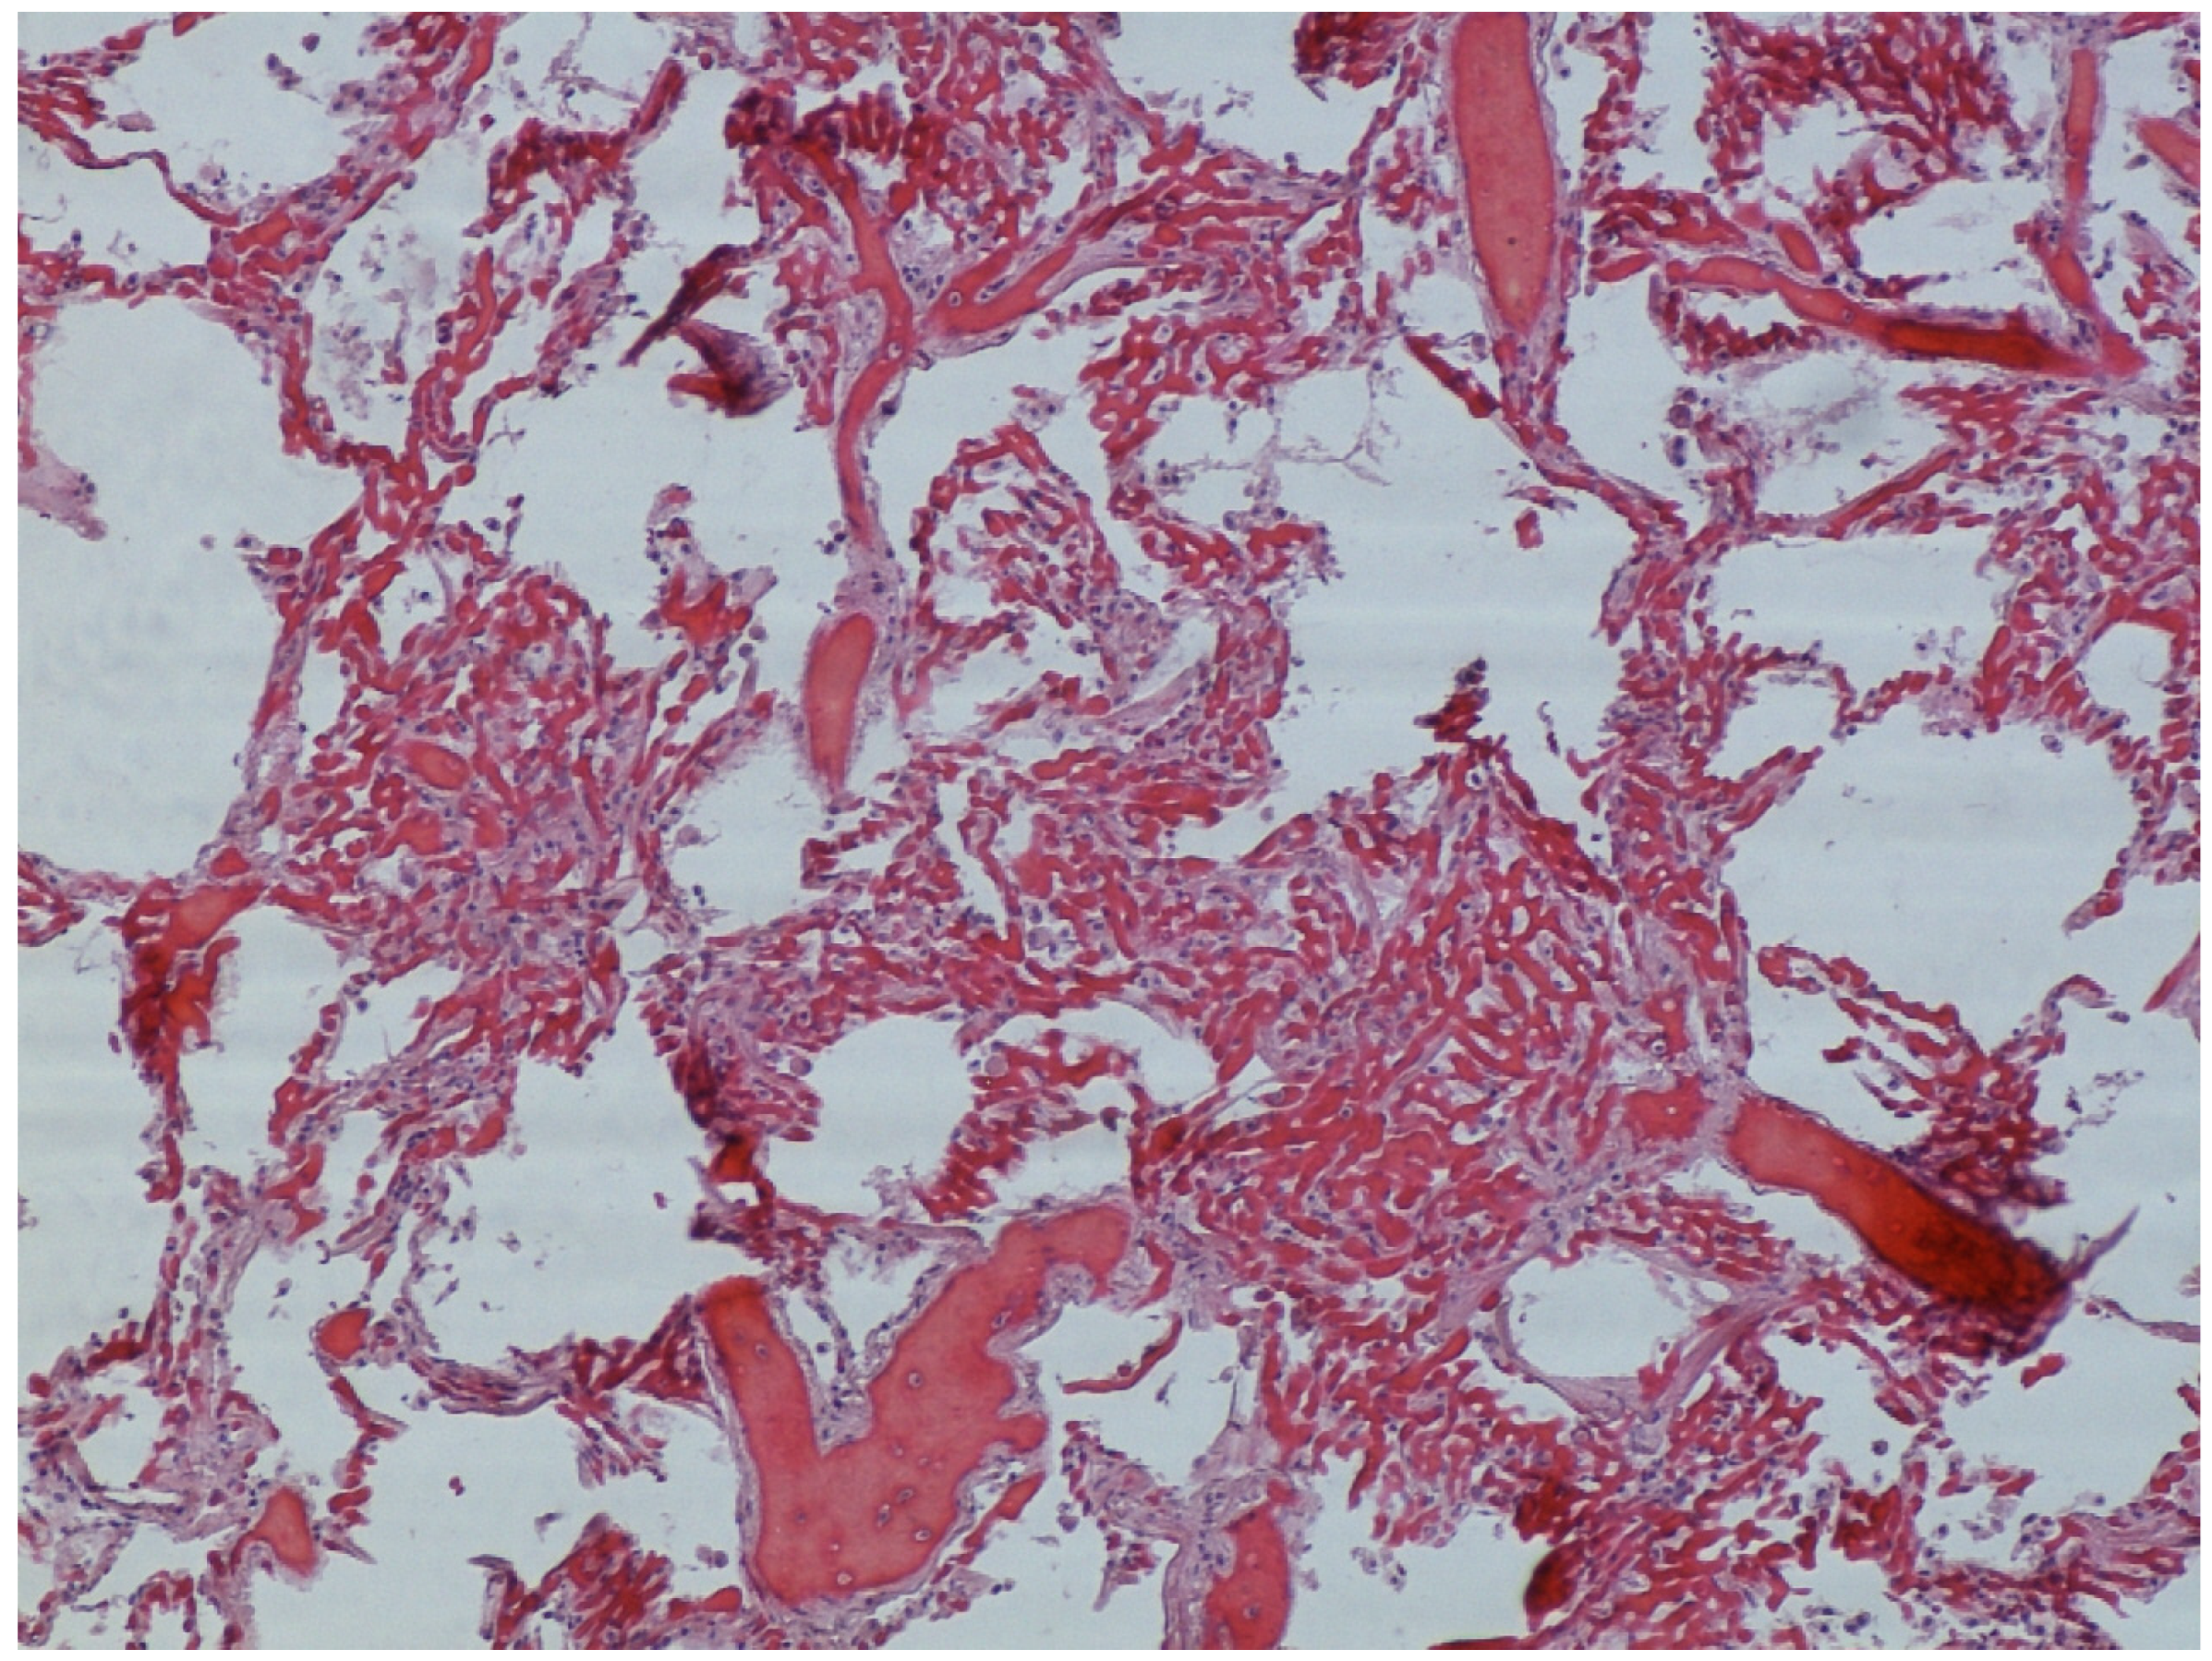

Microscopic observation of tissue sections stained with hematoxylin and eosin showed marked pulmonary congestion (Figure 7), micro- and macrovesicular hepatic steatosis (Figure 8), as well as vacuolization of the basal cells of renal tubules (Figure 9). Gastric wall showed edema and vascular congestion involving mucosa and submucosal layers and focal erosions of the mucosal surface consisting of necrotic foci delimitated by a dense lympho-histiocytic infiltrate (Figure 10). At the level of the skin discoloration (Figure 11), small hemorrhagic extravasations in the dermis were detected.

Figure 7. Pulmonary congestion.